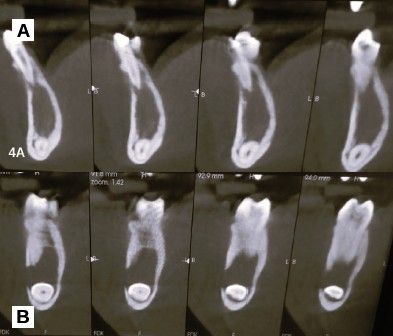

Tras estos hallazgos se solicitóun estudio mediante CBCT mandibular completo, que reveló los siguientes hallazgos en los cortes panorámicos: lesión radiotransparente delimitada y con un halo esclerótico casi completo, que se extiende en sentido mesiodistal desde la zona distal del canino temporal hasta el ápice del primer molar alcanzando la basal mandibular incluyendo la presencia de un canino mandibular (Figura 2).

Los cortes ortorradiales ofrecieron información sobre la ausencia de expansión de corticales, conservación de la cortical lingual y a la altura del segundo premolar ligera perforación de la cortical vestibular (Figuras 3A y 3B). Las reconstrucciones 3D corroboraron los hallazgos anteriormente descritos (Figuras 4A y 4B).